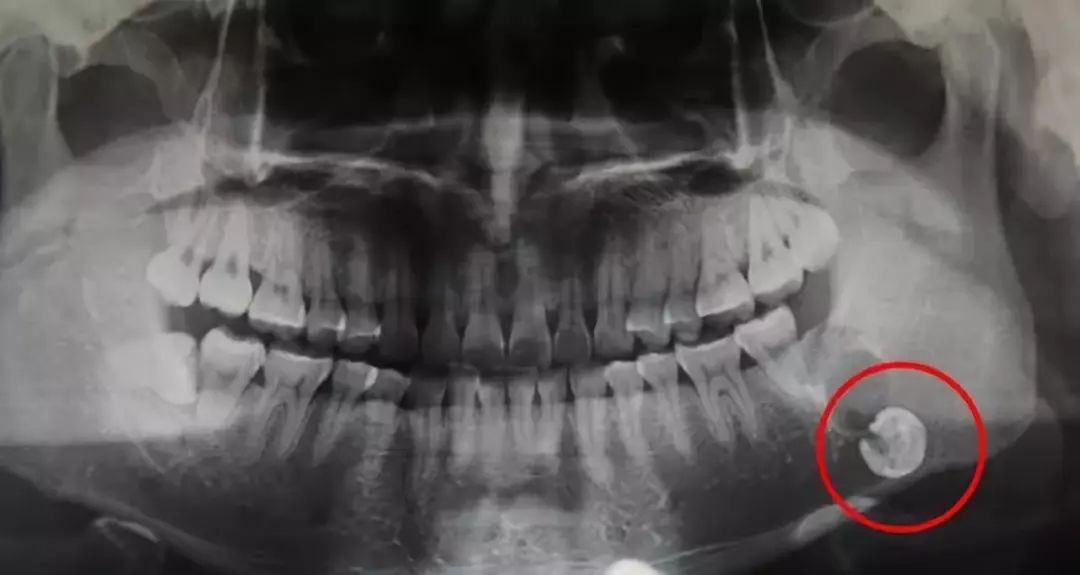

这里还有一颗放飞自我嘅智齿。

最后介绍一下,牙根弯曲,骑在下颌管上嘅智齿...因為下巴管入边嘅神经好丰富,摆脱嚟嘅时候要极度小心,而且看长相也知道这种模式的拔牙,好难同埋好贵!